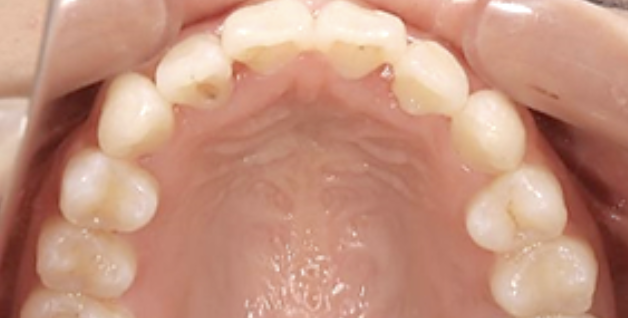

治療前